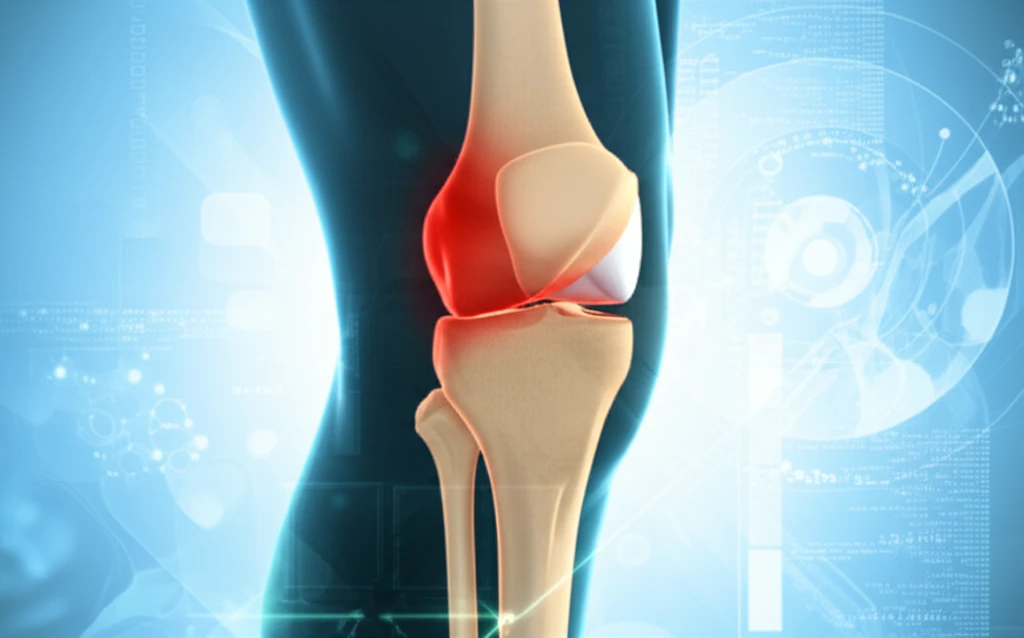

Knee pain is a widespread issue, impacting millions and significantly affecting quality of life. Whether from arthritis, injury, or wear and tear, the discomfort can make everyday activities challenging. While various treatments exist, understanding the mechanics of your knee and how it functions is a crucial step toward effective relief. One key aspect often overlooked is the alignment of the tibia, the large bone in your lower leg, and its relationship with knee health.

The tibia, or shinbone, plays a pivotal role in knee function. It forms the lower part of the knee joint, articulating with the femur (thigh bone) to facilitate movement. Proper alignment of the tibia is crucial for distributing weight evenly across the joint and ensuring smooth, pain-free motion. When the tibia is misaligned, it can lead to increased stress on the joint, accelerating the wear and tear of cartilage and potentially leading to chronic pain and reduced mobility.